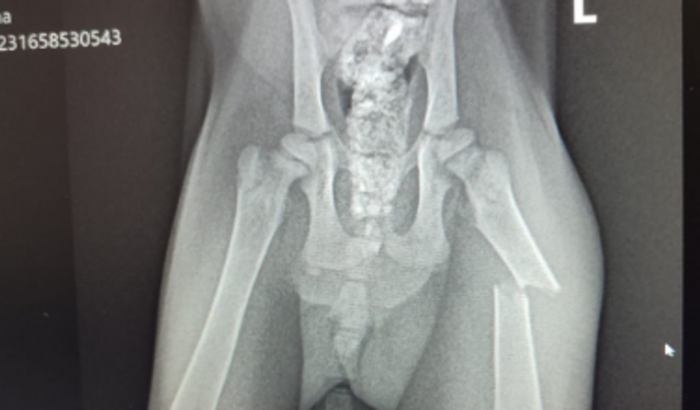

oii gente , sou a protetora de animais Flávia , sou de Gravatal , mas atuo como protetora na ONG de bn , patinhas carentes , bem conhecida. Recebi essa pedido de ajuda pra um gatinho resgatado , ele estava próximo ao motor, entre as correias aí quando o carro foi ligado elas começaram a girar e ele pulou pra fora, já sem aquele pedaço da orelha e arrastando a perninha, foi feito o RAIO X e comprovou a quebra no femur do mesmo , assim que todos os procedimentos forem feitos , a pessoa da qual resgatou o mesmo , ira ficar com ele. Vamos ajudar esse anjinho ? duvidas podem me chamar no insta babixys , whatsapp 48 99668-0519 ou no zap 48 99976-6405. OS VALORES FICARAM DE : - A CIRURGIA FICARÁ NO VALOR DE R$1650 - A ANESTESIA R$200